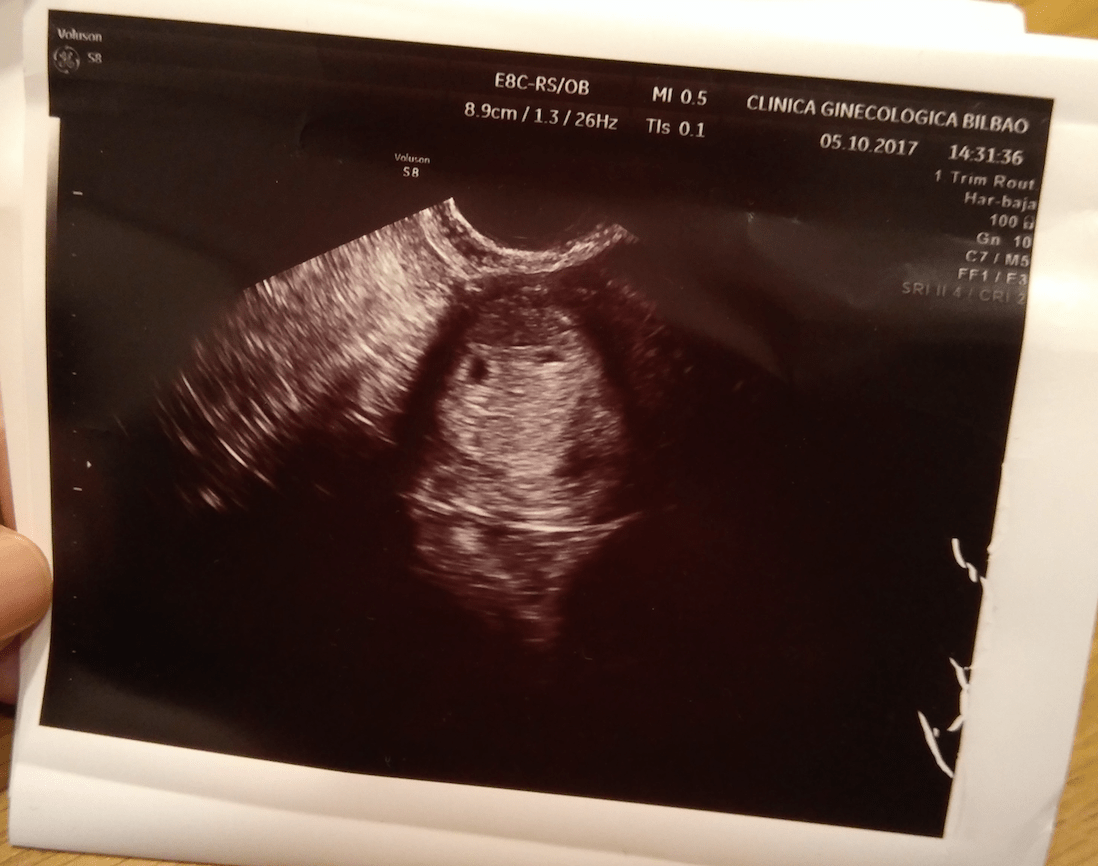

Como ya habíamos tenido una pérdida y tengo seguro privado, nos hicieron la primera ecografía super pronto. El día 5 de Octubre. Hace 10 días. En teoría estaba de 5 + 6, pero recalculando, y como mis ovulaciones son un poco aleatorias, creemos que estaría alrededor de 4 semanas. En esa ecografía no se vieron embriones, pero sí se vieron perfectamente dos bolsitas. DOS. Recreación del momento:

Se ven dos bolsitas que pueden ser el inicio de dos embriones